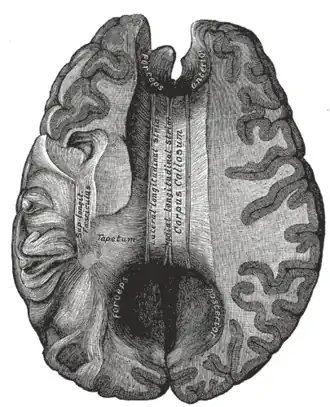

Neuroimaging techniques, such as functional magnetic resonance imaging (fMRI) and positron emission tomography (PET), have shown a correlation between both functional and structural differences in the brains of children with reading difficulties.[38] Some people with dyslexia show less activation in parts of the left hemisphere of the brain involved with reading, such as the inferior frontal gyrus, inferior parietal lobule, and the middle and ventral temporal cortex.[32] Over the past decade, brain activation studies using PET to study language have produced a breakthrough in the understanding of the neural basis of language. Neural bases for the visual lexicon and for auditory verbal short-term memory components have been proposed,[39] with some implication that the observed neural manifestation of developmental dyslexia is task-specific (i.e., functional rather than structural). fMRIs of people with dyslexia indicate an interactive role of the cerebellum and cerebral cortex as well as other brain structures in reading.[40][41]

For most people who are right-hand dominant, the left hemisphere of their brain is more specialized for language processing. With regard to the mechanism of dyslexia, fMRI studies suggest that this specialization is less pronounced or absent in people with dyslexia. In other studies, dyslexia is correlated with anatomical differences in the corpus callosum, the bundle of nerve fibers that connects the left and right hemispheres.[58]

Data via diffusion tensor MRI indicate changes in connectivity or in gray matter density in areas related to reading and language. Finally, the left inferior frontal gyrus has shown differences in phonological processing in people with dyslexia.[58] Neurophysiological and imaging procedures are being used to ascertain phenotypic characteristics in people with dyslexia, thus identifying the effects of dyslexia-related genes.[59]